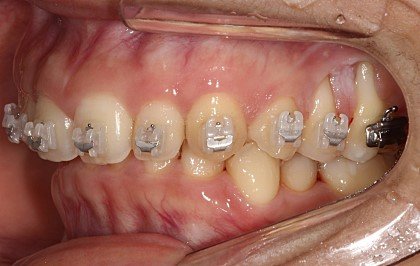

초기진료 때 찍은 잇몸상태 사진을 첨부합니다.

ㄷㅇ치과 원장은 이런 제잇몸 상태를 항상 괜찮다 해왔습니다..사진보고 놀라지 마세요..

ㄷㅇ치과에 초기부터 잇몸이 항상 아프다. 출혈이 자주있고 양치할때도 아파서 잘 못닦는다 하였지만, 대표원장의 대답은 늘 괜찮다는 말이었습니다.

하지만 강남구청역 모 치과 원장님은 이런 잇몸 상태로는 교정하기 힘들다며 치주전문 병원에 연계해 주어 급히 잇몸이식수술을 받아야했습니다

이날도 왼쪽 잇몸이 너무아프고 출혈이 심하게났어서 얘기했지만 괜찮다고 하며 어떤치료도 없었으며, “뿌리가 3개 있는 쪽이라 괜찮다”하길래 믿었습니다.

이곳에서 “현재 잇몸 상태로는 교정을 진행할 수 없으며, 치료와 잇몸 수술 후에 교정해야 하므로 연계 병원에서 수술부터 해야 할 일이다”라는 설명을 들었습니다.

이곳 원장은 저의 상태를 내버려둔 채 교정을 진행해온 사실에 경악하더군요.